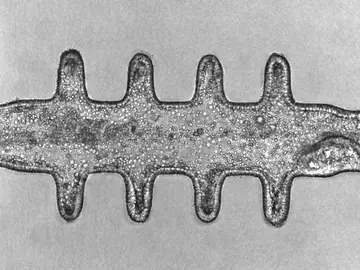

Asocian el parásito Anisakis con cáncer de colon